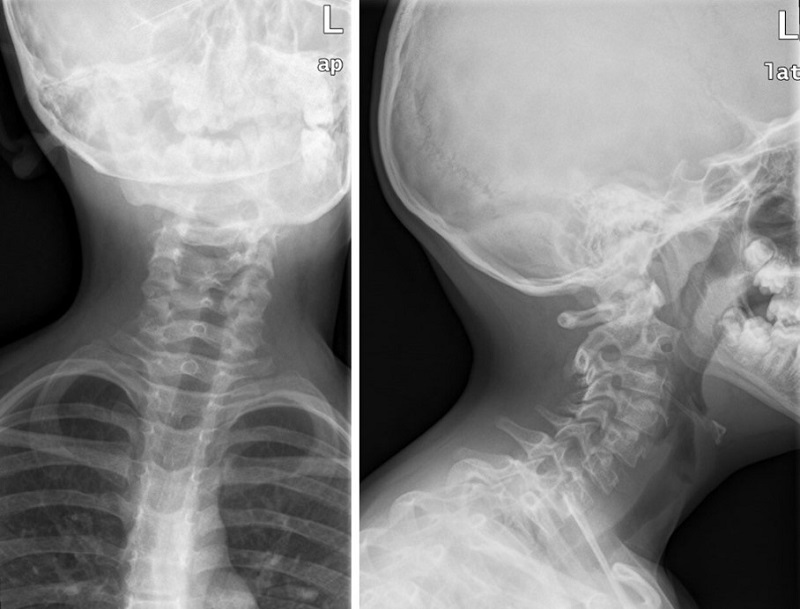

Se realiza radiografía simple (Fig. 1) en la que se aprecia alteración en la alineación de apófisis espinosas y dudosa asimetría de masas laterales del atlas. En el TAC (Fig. 2) se observa desplazamiento de masas laterales de C1 y C2 en relación con subluxación atloaxoidea.

| Figura 1. Radiografía simple en la que se aprecia alteración en la alineación de apófisis espinosas y dudosa asimetría de masas laterales del atlas |